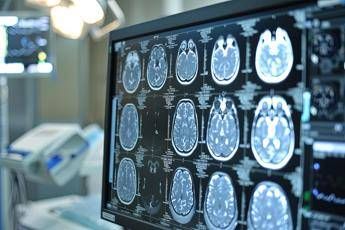

(Adnkronos) – Al convegno Aiic l’esperienza dell’Asl di Salerno con 1 centro hub e 7 spoke collegati “Il progetto di ‘telestroke’ permette ai presidi ospedalieri di periferia (spoke), di ricevere, h24 e 7 giorni su 7, una consulenza neurologica da remoto dai centri di riferimento (hub) per pazienti in cui si sospetta un ictus. L’obiettivo è dare la stessa assistenza in spoke di quella erogata negli hub dove è presente l’unità operativa di neurologia”. Così Maria Biondina ingegnere clinico Hta-Asl Salerno, in occasione de Convegno nazionale dell’Associazione italiana ingegneri clinici (Aiic) in corso a Napoli, racconta l’esperienza di telemedicina nel “conteso territoriale dell’Asl di Salerno – un’area vastissima che ha presidi ospedalieri con alta urbanizzazione vicino a Napoli e una bassa urbanizzazione nel Cilento – che ha previsto un hub con 7 spoke”. Le apparecchiature, “per ogni spoke e hub, si compongono di una stazione robotizzata con un monitor, telecamera e altoparlante per vedere il paziente in televisita o teleconsulto – spiega Biondina – Negli spoke, a differenza degli hub, ci sono anche i dispositivi per la valutazione dei parametri vitali. Le dotazioni dialogano con le strutture aziendali. Per i pazienti con sospetto ictus ischemico che arrivano in pronto soccorso (Ps) di centri spoke, dove non c’è la neurologia, il medico di Ps può chiedere la televisita o condividere esami di imaging diagnostico con il centro hub. Gli spoke di Asl Salerno – precisa l’ingegnere – permettono ai pazienti di effettuare tac e angiotac con o senza mezzo di contrasto visibili al neurologo a decine di chilometri di distanza”. Come è noto la tempestività della diagnosi e della terapia “riducono i danni da ictus – sottolinea l’esperta – per questo la rapida presa in carico del paziente fa la differenza: attivando, da parte del medico di ps il contatto con il neurologo da remoto, nel giro di circa 40 minuti permette di gestire il paziente attivando la trombolisi endovenosa ed evitare la trobectomia meccanica, procedura più invasiva, che comporta anche il trasferimento ad altra struttura. Nel giro di un anno – tra febbraio 2024 e marzo 2025 – ci sono state 261 connessioni – conclude – L’obiettivo è di ampliare l’impiego di questo modello anche per la rete cardiologica”. —salutewebinfo@adnkronos.com (Web Info)